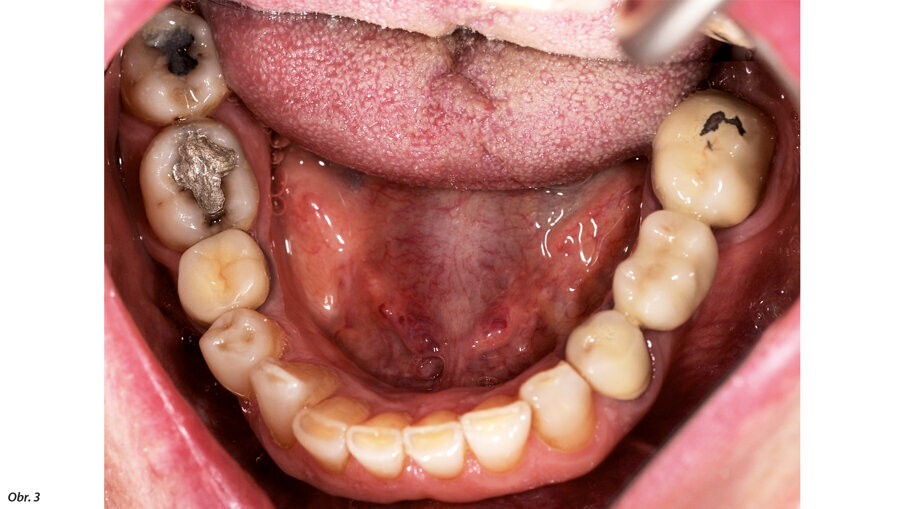

66letý pacient s non-inzulin dependentním diabetes mellitus a ischemickou chorobou srdeční se dostavil na ošetření parodontálního abscesu v oblasti radix relicta 12 a vícečetných fraktur stávajících náhrad (obr. 1–6). Během návštěvy byla zjištěna značná malokluze a ztráta VRO, abraze a fraktury stávajících náhrad i zbylých zubů a známky cervikální abfrakce. Pacient také trpěl mírnou bolestivostí svalů při palpaci, a to zejména v oblasti m. pterygoideus medialis et lateralis, sníženou schopností otevírání úst a slabými zvukovými fenomény v oblasti temporomandibulárních kloubů.